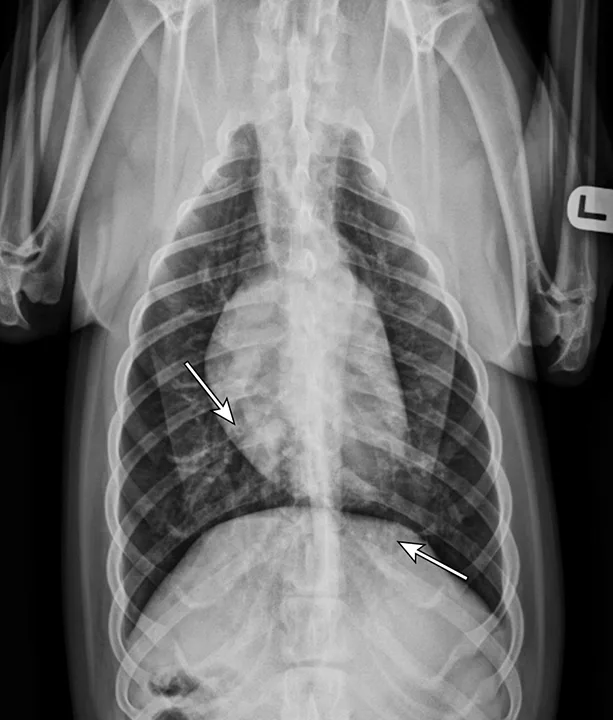

At 1 month after discharge, thoracic radiography was repeated and revealed marked improvement in diffusion of the bronchointerstitial pattern (Figure 4). Prednisone was tapered over the next 6 weeks to 10 mg every other day. Intermittent coughing returned, and the dosage was increased to 10 mg once daily (0.33 mg/kg/day), which maintained clinical control. Because this regimen did not result in significant adverse effects and maintained clinical control, adjunctive or alternative anti-inflammatory medications were not prescribed.

Radiograph 1 month after therapeutic initiation showing an improved bronchointerstitial pattern

Thoracic radiographs are generally characterized by a diffuse bronchointerstitial pattern with peribronchial cuffing and thickening of the bronchial walls. In some cases, bronchiectasis or alveolar infiltration may be observed.2,6-8 Occasionally, patchy pulmonary opacities create a nodular appearance.4 Radiography is critical for ruling out other common causes of cough and/or acute respiratory distress. Concurrent disease processes (eg, cardiomegaly, tracheal collapse) can complicate diagnosis.